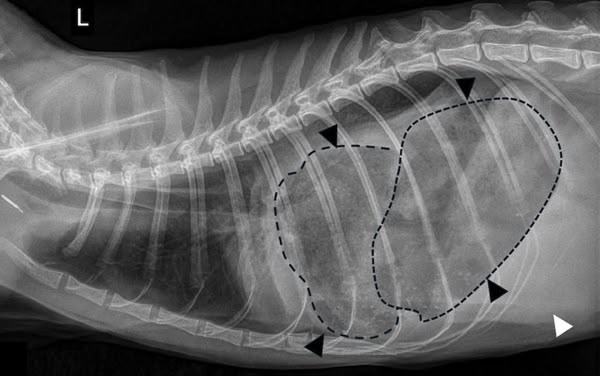

Figure 1

Figure 2